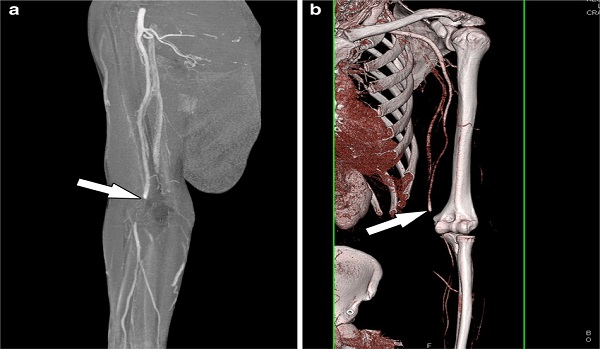

Our CT Extremity service provides high-resolution imaging of the bones, joints, and soft tissues in the arms, legs, hands, and feet.

This advanced imaging technique is crucial for diagnosing fractures, joint abnormalities, soft tissue injuries, and other musculoskeletal conditions. The non-invasive scan offers detailed cross-sectional views, enabling precise diagnosis and aiding in effective treatment planning